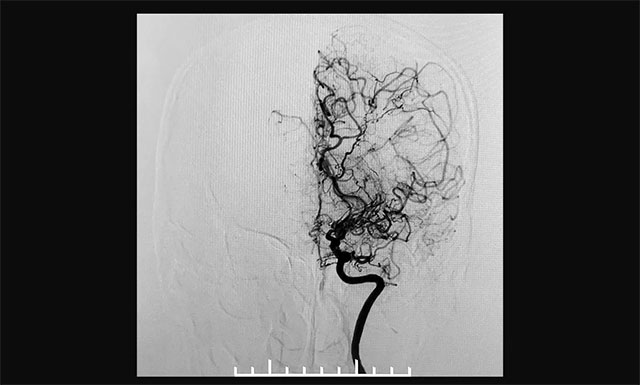

患者头颅CTA示,左侧大脑后动脉P1段偏细,相应左侧后交通代偿性增粗。DSA检查显示双侧颈内动脉闭塞,可见异常血管形成,右侧颈内动脉未向颅内供血,右侧大脑后动脉通过皮层软膜血管向右侧大脑前、中动脉代偿。既往有“高血压”病史6年,收缩压最高为180毫米汞柱,平时血压控制欠佳。结合病史患者确诊为烟雾病。

▲ 术前造影显示,患者双侧颈内动脉末端闭塞,颅内烟雾状血管形成